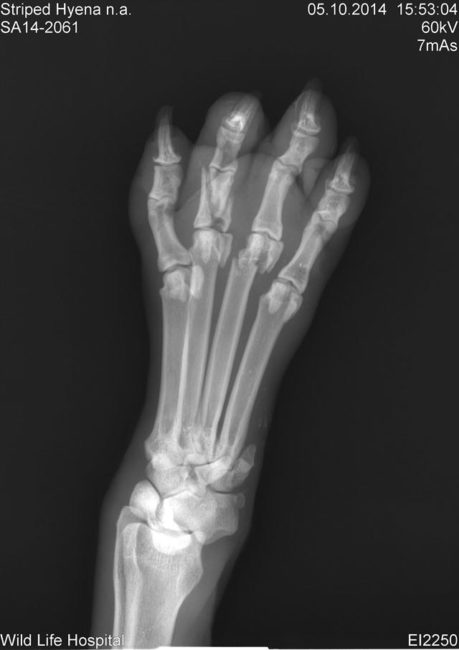

Ο χειρότερος τραυματισμός του ήταν πως είχε σπασμένο μπροστινό πόδι και πατούσα. Φάνηκε σαν να είχε πιαστεί σε κάποια παγίδα και αυτό θα μπορούσε να εξηγήσει τον τρόπο που βρέθηκε σε αιχμαλωσία.